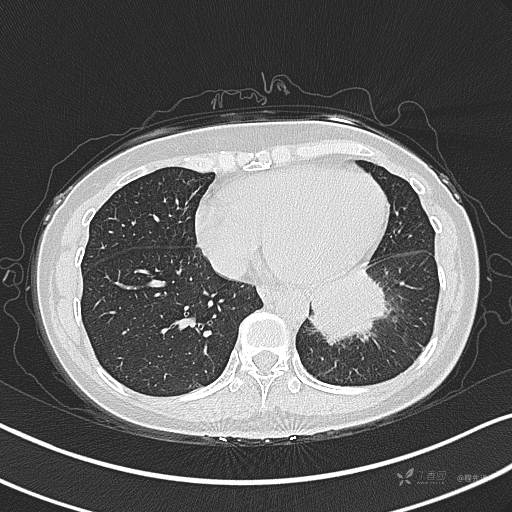

CT平扫

肺窗